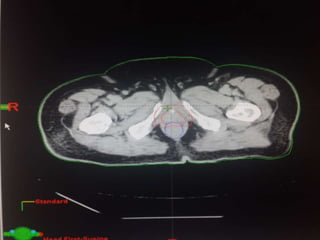

RTOG GU Consensus on pelvic LN CTV volumes:

 Commence contouring the pelvic CTV LN volumes at the L5/ S1

interspace (the level of the distal common iliac and proximal

presacral lymph nodes).

 Place a 7-mm margin around the iliac vessels connecting the

external and internal iliac contours on each slice, carving out

bowel, bladder, and bone.

 Contour presacral lymph nodes from S1 through S3, posterior

border being the anterior sacrum, and anterior border

approximately 10 mm anterior to the anterior sacral bone

carving out bowel, bladder, and bone.

 Stop external iliac CTV lymph node contours at the top of the

femoral heads (bony landmark for the inguinal ligament).

 Stop contours of the obturator CTV lymph nodes at the top of

the symphysis pubis.

Our unit decide to treat:

 Prostate + S.V & prophylactic Pelvic LNs in

phase1

 Prostate + S.V phase 2

 Delineation of our unit illustrated in the

following slides:

RTOG GU Consensuson pelvic LN CTV volumes:  Commence contouring the pelvic CTV LN volumes at the L5/ S1 interspace (the level of the distal common iliac and proximal presacral lymph nodes).  Place a 7-mm margin around the iliac vessels connecting the external and internal iliac contours on each slice, carving out bowel, bladder, and bone.  Contour presacral lymph nodes from S1 through S3, posterior border being the anterior sacrum, and anterior border approximately 10 mm anterior to the anterior sacral bone carving out bowel, bladder, and bone.  Stop external iliac CTV lymph node contours at the top of the femoral heads (bony landmark for the inguinal ligament).  Stop contours of the obturator CTV lymph nodes at the top of the symphysis pubis.

Our unit decideto treat:  Prostate + S.V & prophylactic Pelvic LNs in phase1  Prostate + S.V phase 2  Delineation of our unit illustrated in the following slides: